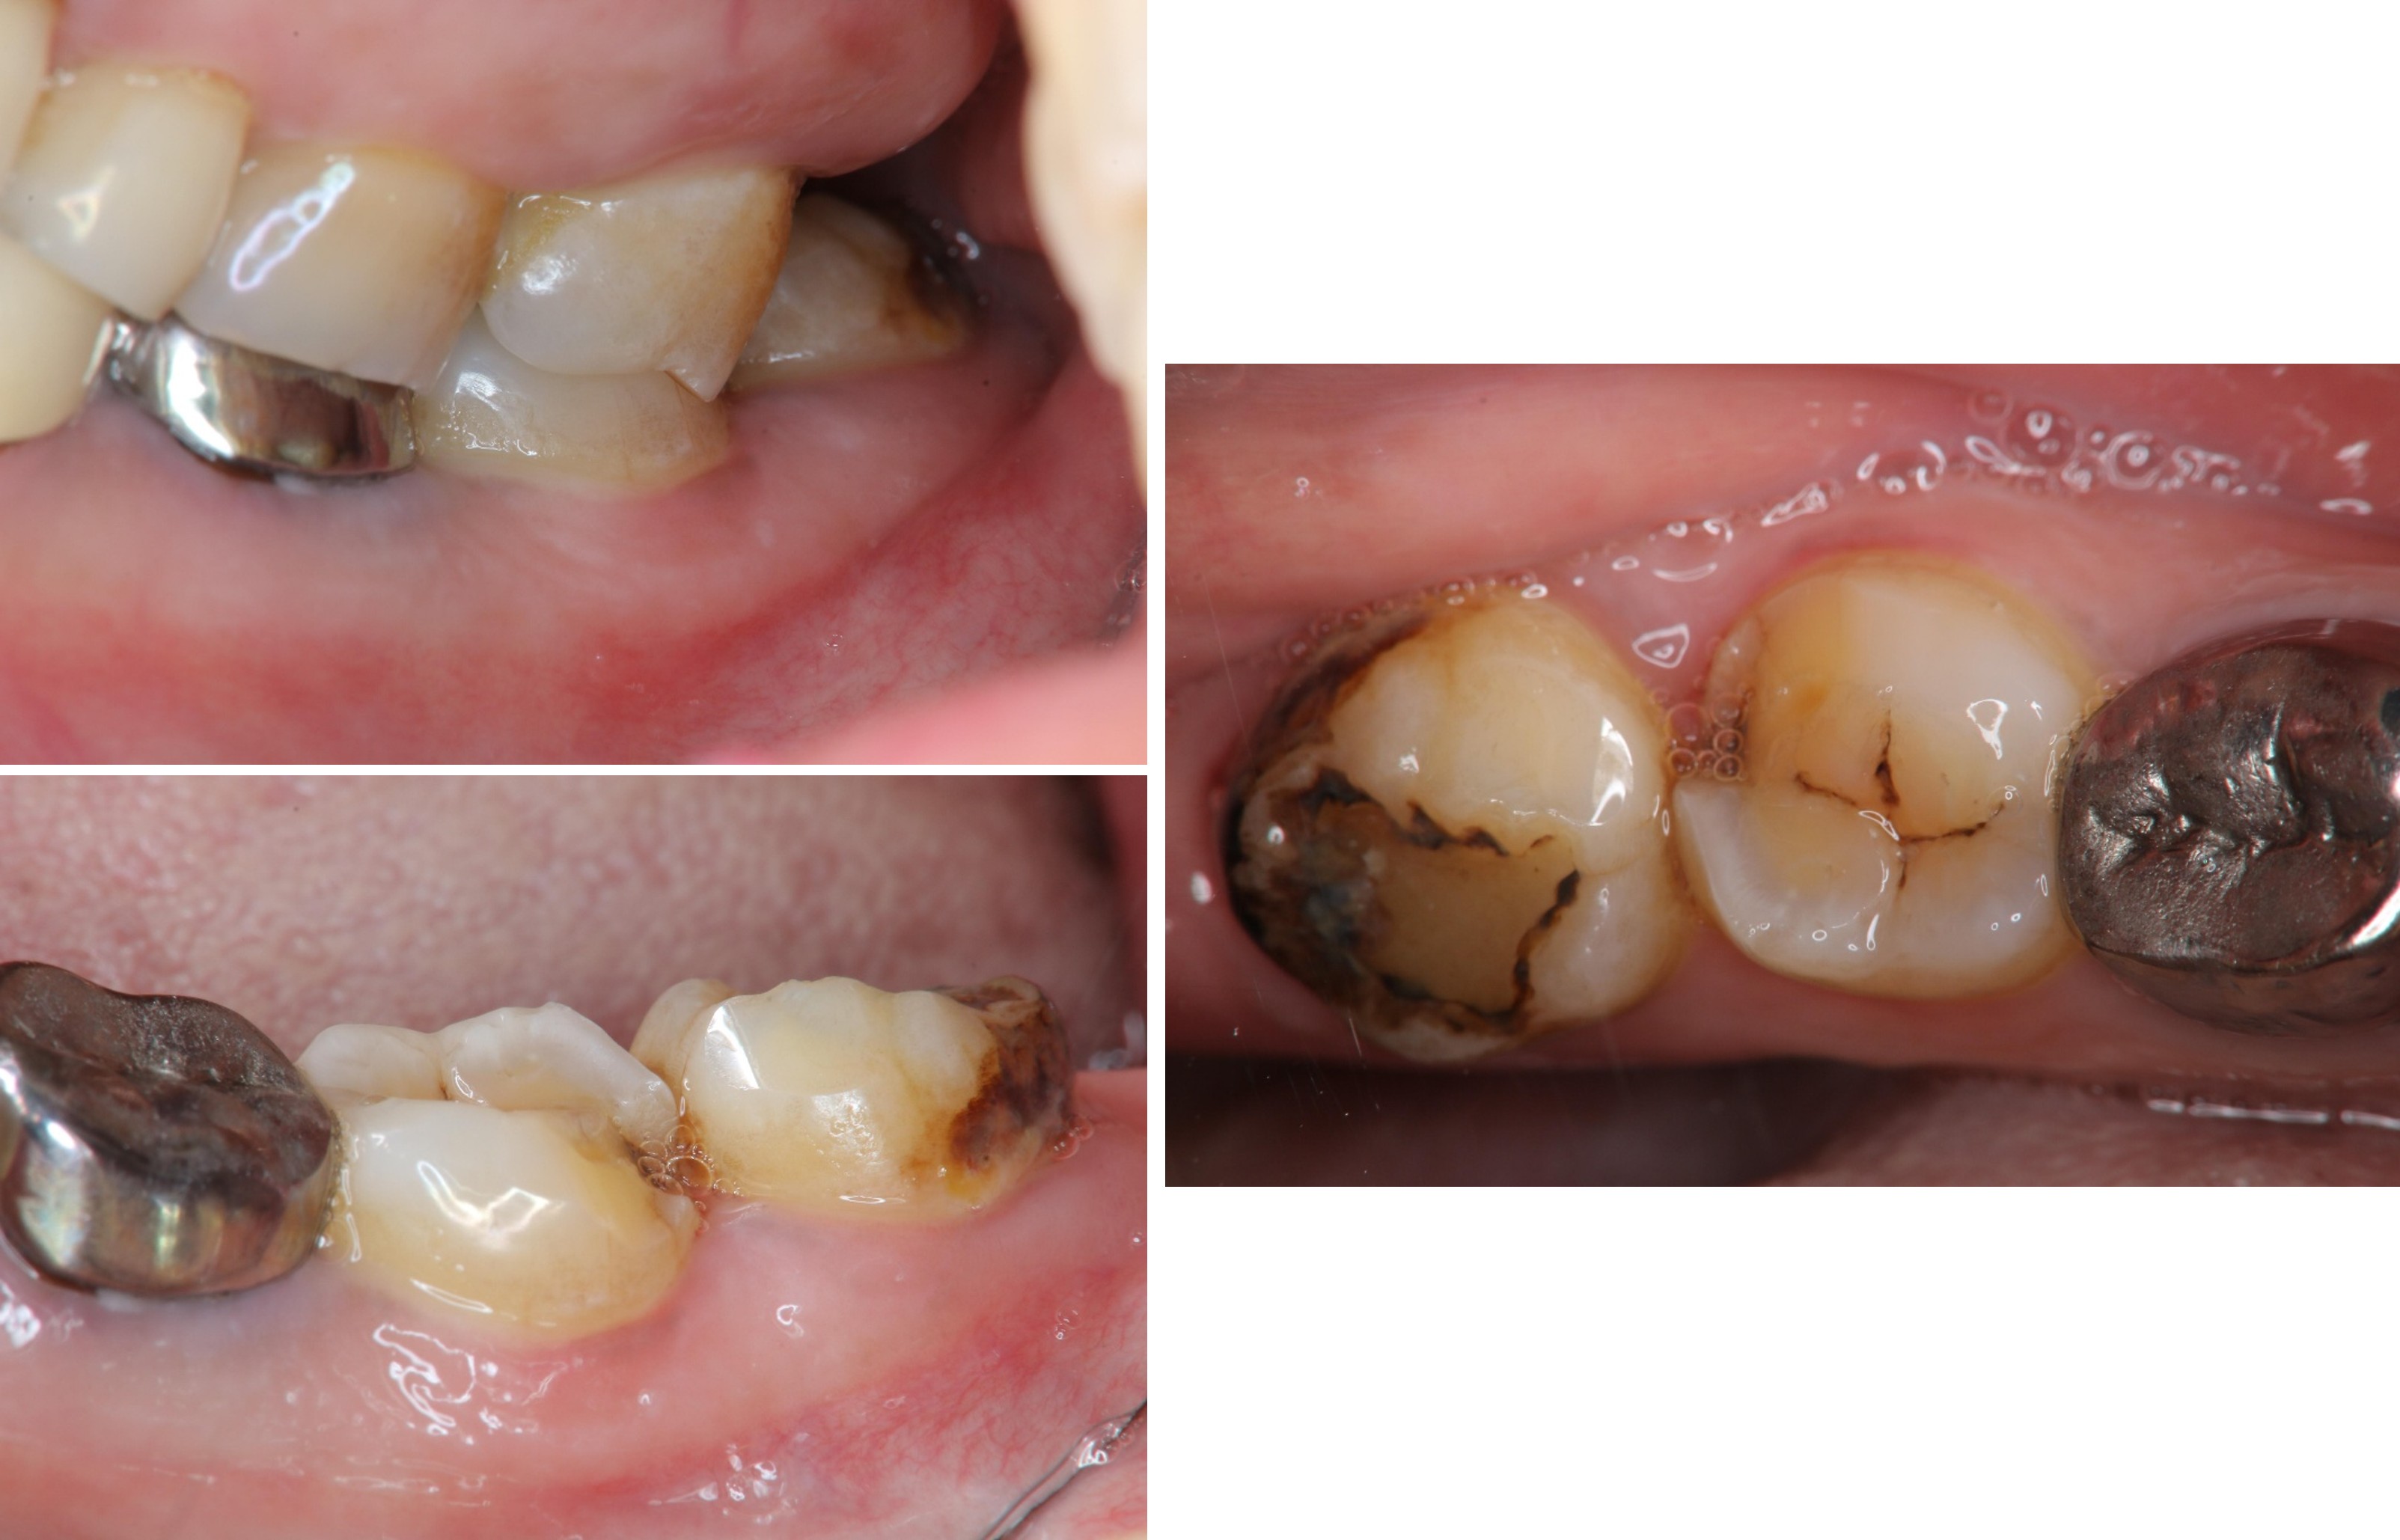

治療前,左下第二大臼齒蛀牙

治療前,左下第二大臼齒根管鈣化